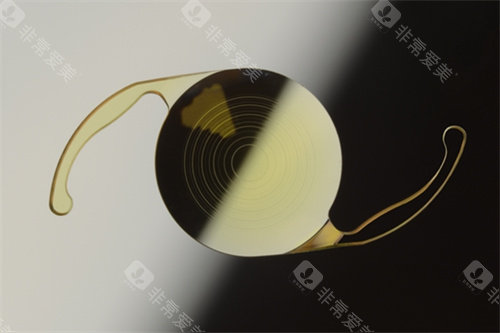

进口人工晶体常采用疏水性丙烯酸酯、硅胶等高端材料。

以美国眼力健的消色差晶体为例,其通过特殊涂层技术,能主动过滤紫外线与蓝光,减少术后眩光问题;德国蔡司的409晶体则以“409兆像素级分辨率”著称,色彩还原度接近自然视觉。

这些材料不仅生物相容性更优,还能降低后囊混浊风险,延长晶体使用寿命。